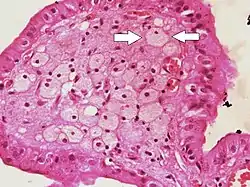

Foam cells (one indicated by arrows) visible in the finger-like projections into the gallbladder lumen in a case of cholesterolosis

Foam cells, also called lipid-laden macrophages, are a type of cell that contain cholesterol. These can form a plaque that can lead to atherosclerosis and trigger myocardial infarction and stroke.[1][2][3]

Foam cells are fat-laden cells with a M2 macrophage-like phenotype. They contain low density lipoproteins (LDL) and can only be truly detected by examining a fatty plaque under a microscope after it is removed from the body.[4] They are named because the lipoproteins give the cell a foamy appearance.[5]